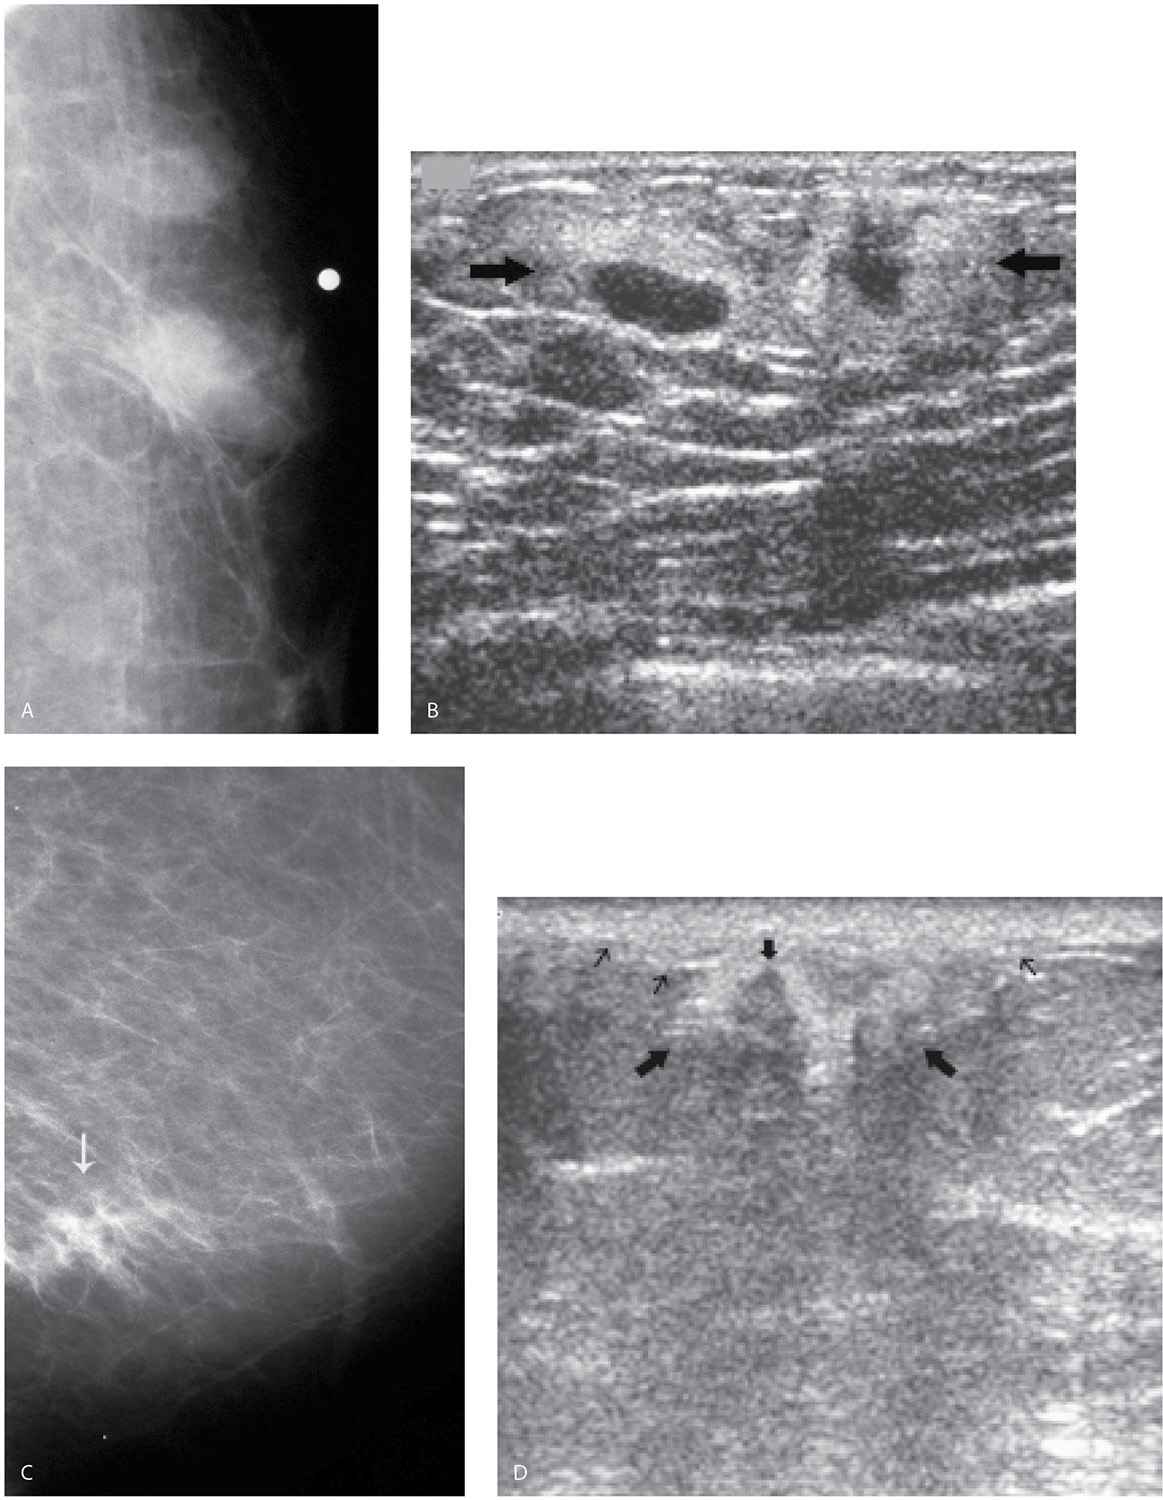

Ultrasound images of the retroareolar region. A) Normal male breast... Download Scientific Diagram Ultrasound For Male Breast Lump Here we describe the normal male breast anatomy and present an evaluation algorithm for the male patient with breast signs or symptoms. We discuss the demographics of male breast. A complete breast exam will be done to find any lumps or suspicious areas and to feel their texture, size, and relationship to the skin and. Male breast imaging is mostly. Ultrasound For Male Breast Lump.